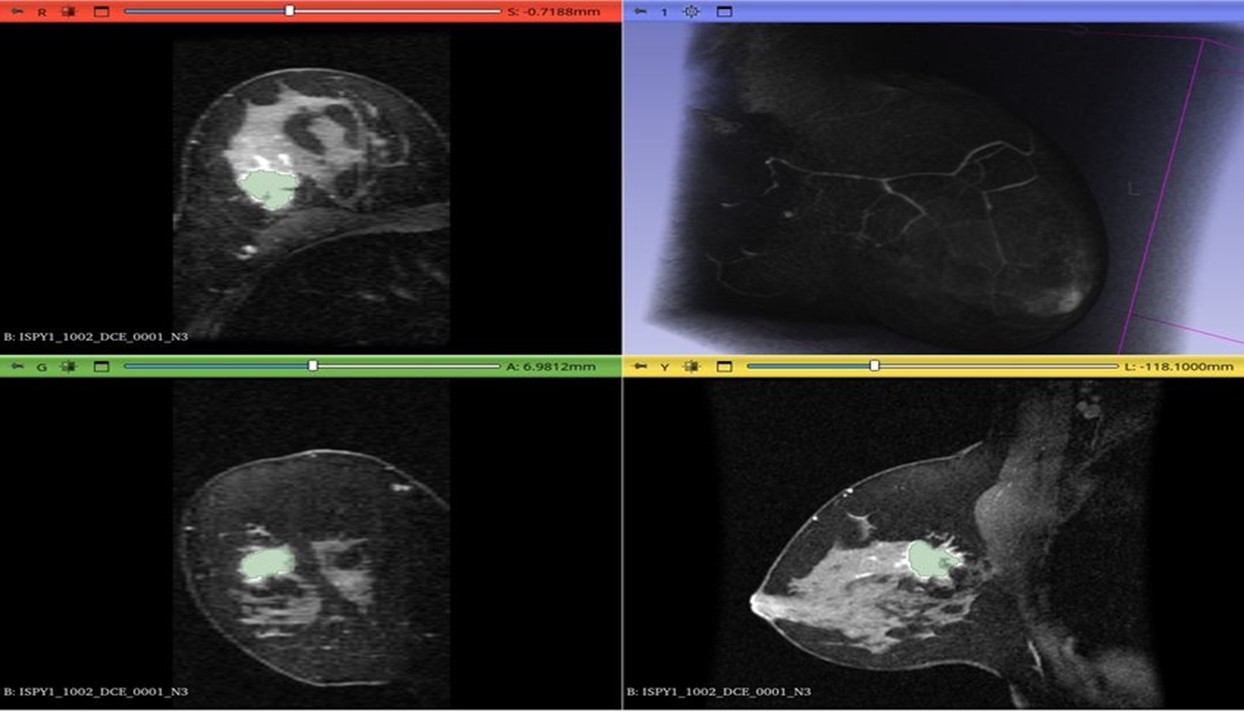

Диагностика РМЖ с интеграцией ИИ

• Будут разработаны алгоритмы глубоких нейронных сетей для диагностики рака молочной железы на основе данных маммографии.

• разработаны алгоритмы глубоких нейронных сетей для диагностики рака молочной железы на основе данных маммографии